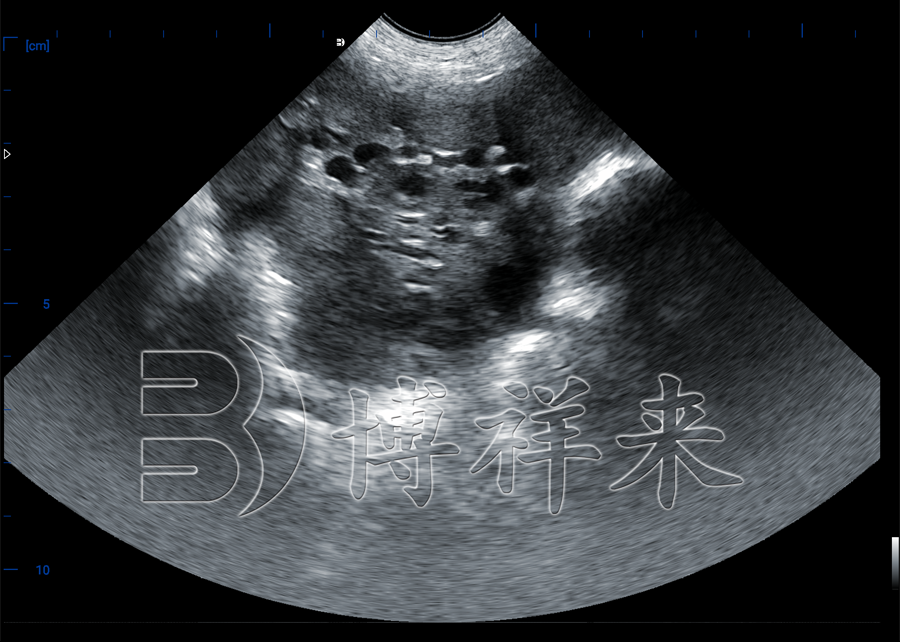

猪用B超机是一种专业兽用超声设备,采用B-mode(二维)超声技术,配合高频探头(如3.5 MHz、5 MHz或7.5 MHz),主要用于监测母猪卵泡发育、估测排卵时间、早孕检测及子宫健康评估。

实时监测卵泡直径(如识别成熟卵泡 ≥ 7 mm,排卵前期卵泡形态的变化),对母猪无应激,无需给药 。

卵泡从7‑9 mm到成熟状态仅需短短几天,通过B超检测可精准判定排卵期,合理安排人工授精或配种时间 。

2、操作流程:略去毛发、涂耦合剂 → 探头放置于腹侧乳头后部 → 扫描观测卵泡图像 → 冻结测量直径。